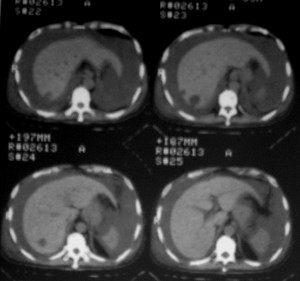

m ,60岁,右上肺ca术后一月。

右侧肺癌术后:肝内可见多个大小不等的低密度结节影。腹腔及双侧胸腔大量积液。考虑:肺癌并胸膜及肝脏转移。

纵隔淋巴结增大,双侧胸水。考虑术后残留,而非复发。

腹水,肝及右肾多发低密度影。考虑转移。

1、右肺癌术后改变。2、双侧胸水、腹水。3、多发性肝囊肿,右侧肾囊肿。

目前转移或复发的依据不足,术后才一个月,个人认为还是让临床去判断,而且需结合术前常规检查,有无肝肾囊肿;另外有一个疑问:肝胃间隙内团状软组织影是胃食管交接区吗,胃腔太小了吧,有无手术史请楼主告知.